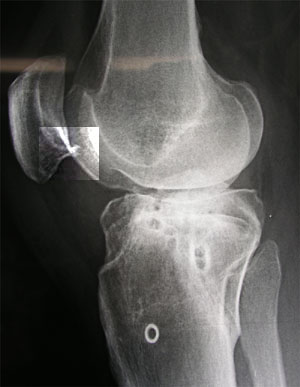

Der Röntgencheck in Chur brachte eine besorgniserregende Erkenntnis: Die Schmerzen am unteren Patellarand könnten von einer bereits beginnenden Arthrose herrühren (siehe weiter unten). Ansonsten hab ich wieder eine Lizenz zum Skifahren - und die Gewissheit, dass ich keine grössere Schwellung mehr im Knie habe. Und immerhin bin ich vom Metall befreit... ausser dem "Heiligenschein" rechts unten, einer eingewachsenen Unterlagsscheibe, die immerhin dereinst Angestellte eines Bestattungsunternehmens beschäftigen wird: "Wie finden wir das kleine Ding, das in dieser Urne so klimpert?" - Die folgende Bilderserie zeigt der Verlauf von den Schrauben der ersten OP über diejenigen der Korrekturosteotomie vom April 2002 bis zum Dezember 2002.

Sie können auf die einzelnen Bildfragmente klicken, um eine grössere Fassung des Ausschnittes zu sehen.

Sorgen macht die Kniescheibe: Auf der folgenden Bilderserie von Mai 2001 bis Dezember 2002 (aufs Bild klicken für Originalgrösse!) ist deutlich sichtbar, wie sich am linken unteren Patellarand ein kleiner Höcker gegen das Wadenbein hin bildet. Dieser Auswuchs (Osteophyt) könnte der Grund für den noch vorhandenen Hauptschmerz sein; er könnte auch vom Bechterew herrühren oder durch diese Krankheit zumindest verstärkt worden sein.

Ebenfalls gut zu sehen ist jedoch die schöne Heilung der ursprünglichen Bruchstelle (links unten im Bild) - einen Monat nach der Operation (links) klafft noch eine deutliche Lücke, die im Lauf der Zeit von neuer Knochenstruktur überwachsen wird.

In diesem Röntgenbild (für einmal von der anderen Seite aufgenommen) von Anfang Dezember 2002 (Inselspital Bern, anlässlich der Punktion - aufs Bild klicken für grössere Fassung) sieht man wiederum schön den mutmasslichen Osteophyten an der Patella, den ich immer mehr für die Schmerzen verantwortlich mache, die nunmehr seit einem halben Jahr andauern.

Hier ist eine Ausschnittsvergrösserung der unteren Patellareagion zu sehen (im Bild oben eingerahmt).